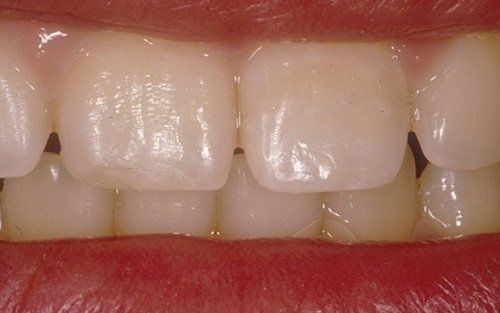

I denti da latte traumatizzati più spesso vanno incontro a necrosi con conseguente cambiamento di colore, divenendo grigiastri, segno della morte delle cellule della polpa dentaria. In altre occasioni, il dente può fratturarsi in maniera più o meno ampia: se il frammento viene ritrovato, potrà essere re-incollato in maniera invisibile, oppure verrà ricostruito con i materiali compositi.